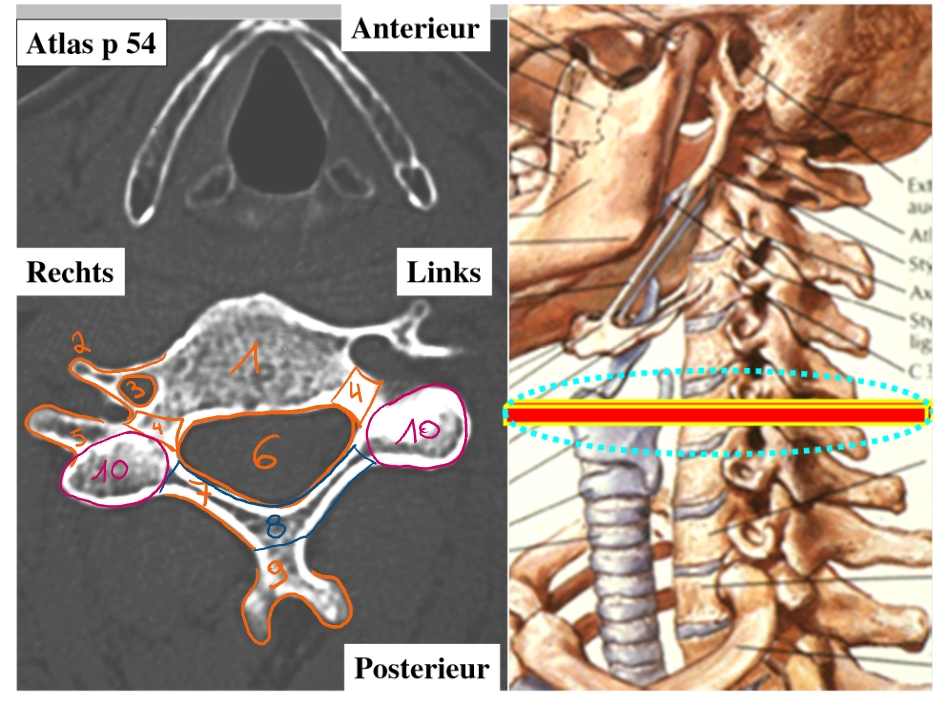

CT-scan

maakt dwarse doorsneden van de mens → salami

corpus

tuberculum anterius

foramen transversarium

arteria vertebralis gaat hierdoor

pedikel

tuberculum posterius

foramen vertebrale

lamina

helft van de arcus

arcus

processus spinosus

massa lateralis/ articulaire pijler/ pars interarticularis